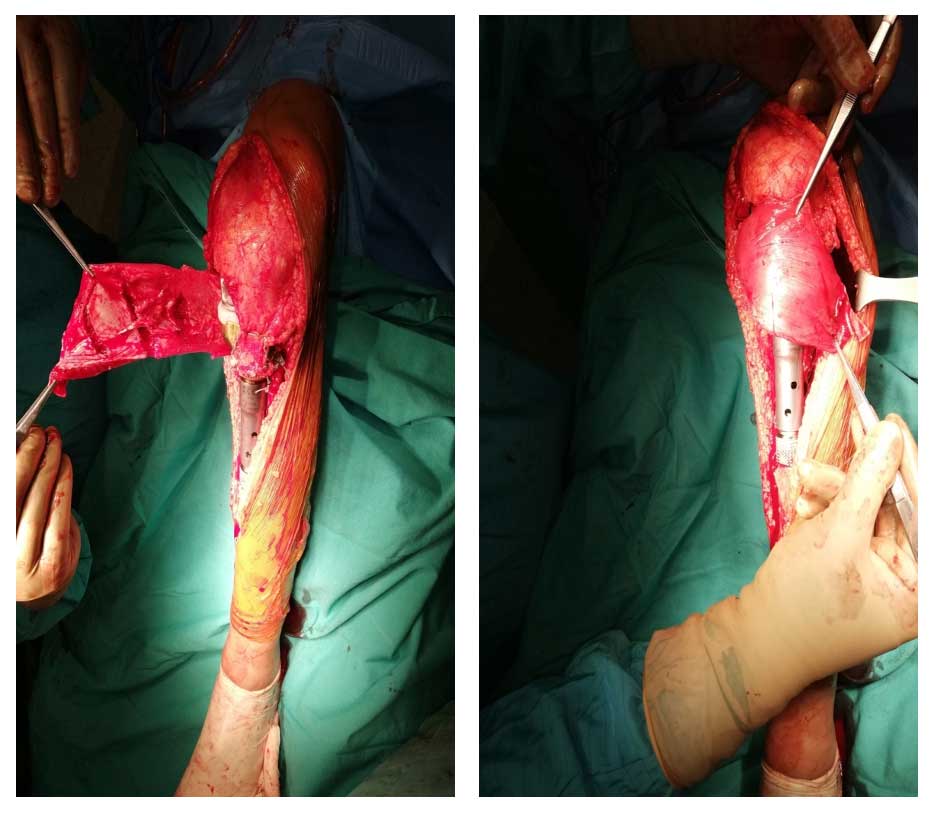

Ameliyat Esnası: Rezeksiyon ve tümör protez yerleşimi sonrası patellar tendon stürasyonu ve gastroknemius flep örtümü görülmekte.